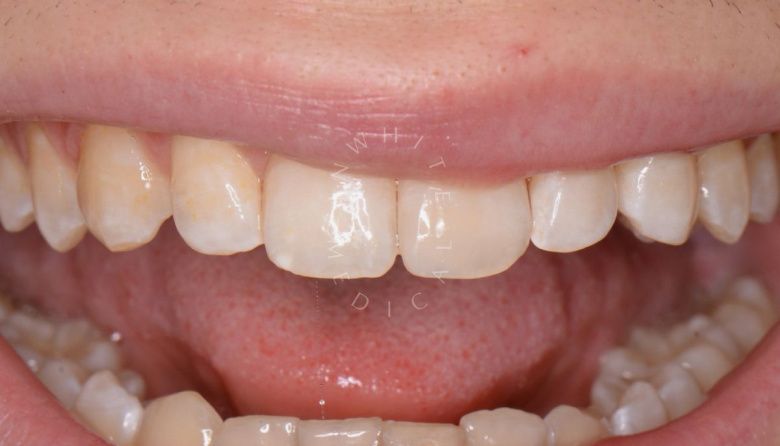

Художественная реставрация формы зубов

Стоматология Москва лучшие клиники. Художественная реставрация формы зубов - до процедуры